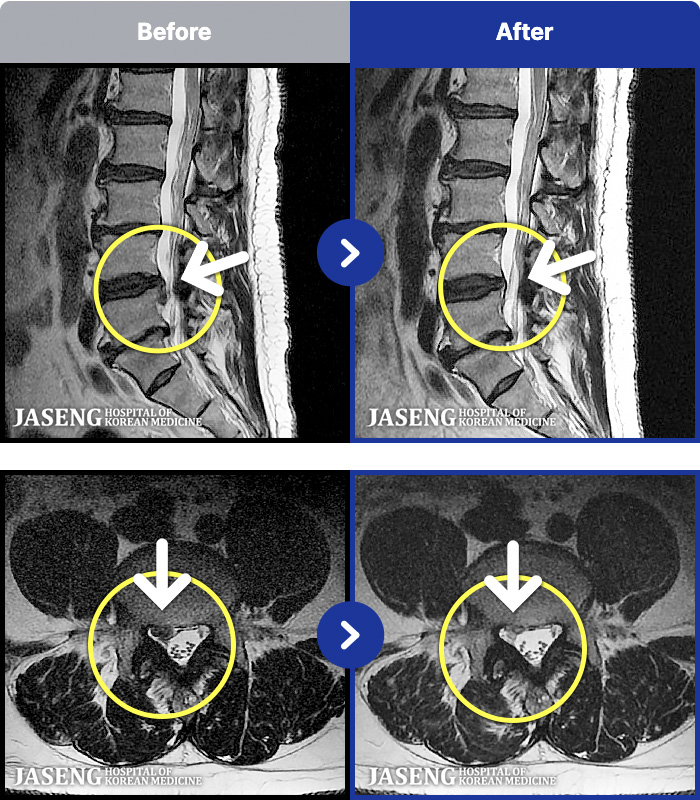

[Կñ:21.12.17~22.07.04]

[_㸮ũ] 㸮

No.53

ȸ 204